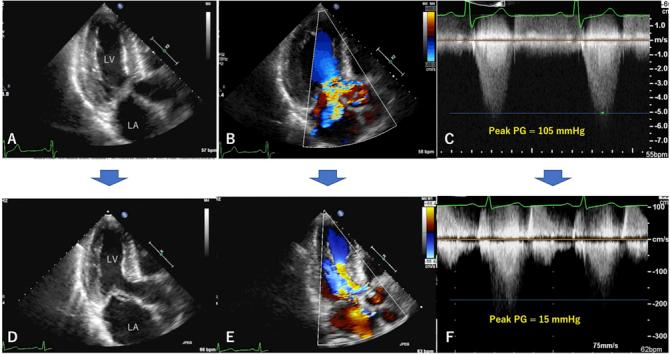

肥厚型心肌病患者二尖瓣腱索自发断裂后左心室流出道梗阻完全缓解

Complete Resolution of Left Ventricular Outflow Tract Obstruction After Spontaneous Mitral Valve Chordal Rupture in a Patient With Hypertrophic Cardiomyopathy.

• Spontaneous mitral chordal rupture is a complication in hypertrophic cardiomyopathy (HCM). • Mitral chordal rupture in HCM causes deterioration in heart failure. • Symptoms improved when left ventricular outflow tract (LVOT) obstruction disappeared. • Mitral valve has a role in LVOT obstruction and systolic anterior motion.

• 自发性二尖瓣腱索断裂是肥厚型心肌病(HCM)的一种并发症。

• 肥厚型心肌病中的二尖瓣腱索断裂会导致心力衰竭恶化。

• 当左心室流出道(LVOT)梗阻消失时,症状改善。

• 二尖瓣在左心室流出道梗阻和收缩期前向运动中起作用。